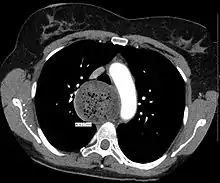

An axial CT image showing marked dilatation of the esophagus in a person with achalasia.